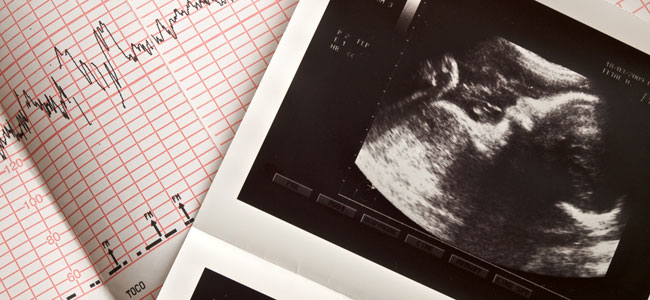

Durante el embarazo, el bebé se encuentra muy protegido respecto a un eventual problema de tiroides. Por un lado, tiene la posibilidad de usar las hormonas que el mismo fabrica o utilizar las de su madre que pasan a través de la placenta. Así, si el embrión o el feto padecen una falta congénita de tiroides, puede utilizar las hormonas que le suministra su madre. Por el contrario, si es su madre la que tiene un hipotiroidismo severo, el bebé podrá usar las hormonas que él fabrica. En ambos casos, el niño nacerá absolutamente normal en su desarrollo.Te explicamos cómo afecta el hipertiroidismo en el feto.

El problema sucede cuando hay una falta de yodo para la fabricación de las hormonas tiroideas. En estas circunstancias no funciona bien ni el tiroides de la madre ni el del feto, y entonces sí hay problemas. Utilizar sal yodada en las comidas es la mejor manera de asegurarse una ingesta en yodo adecuada.

Pero cuando falta yodo, la tiroides de la madre no puede fabricar la cantidad de hormona tiroidea necesaria, la TSH de la madre se eleva y la tiroides de la madre crece. Al feto le pasa lo mismo y tambien puede nacer con un pequeño bocio, aparte de los problemas de desarrollo que haya podido tener.